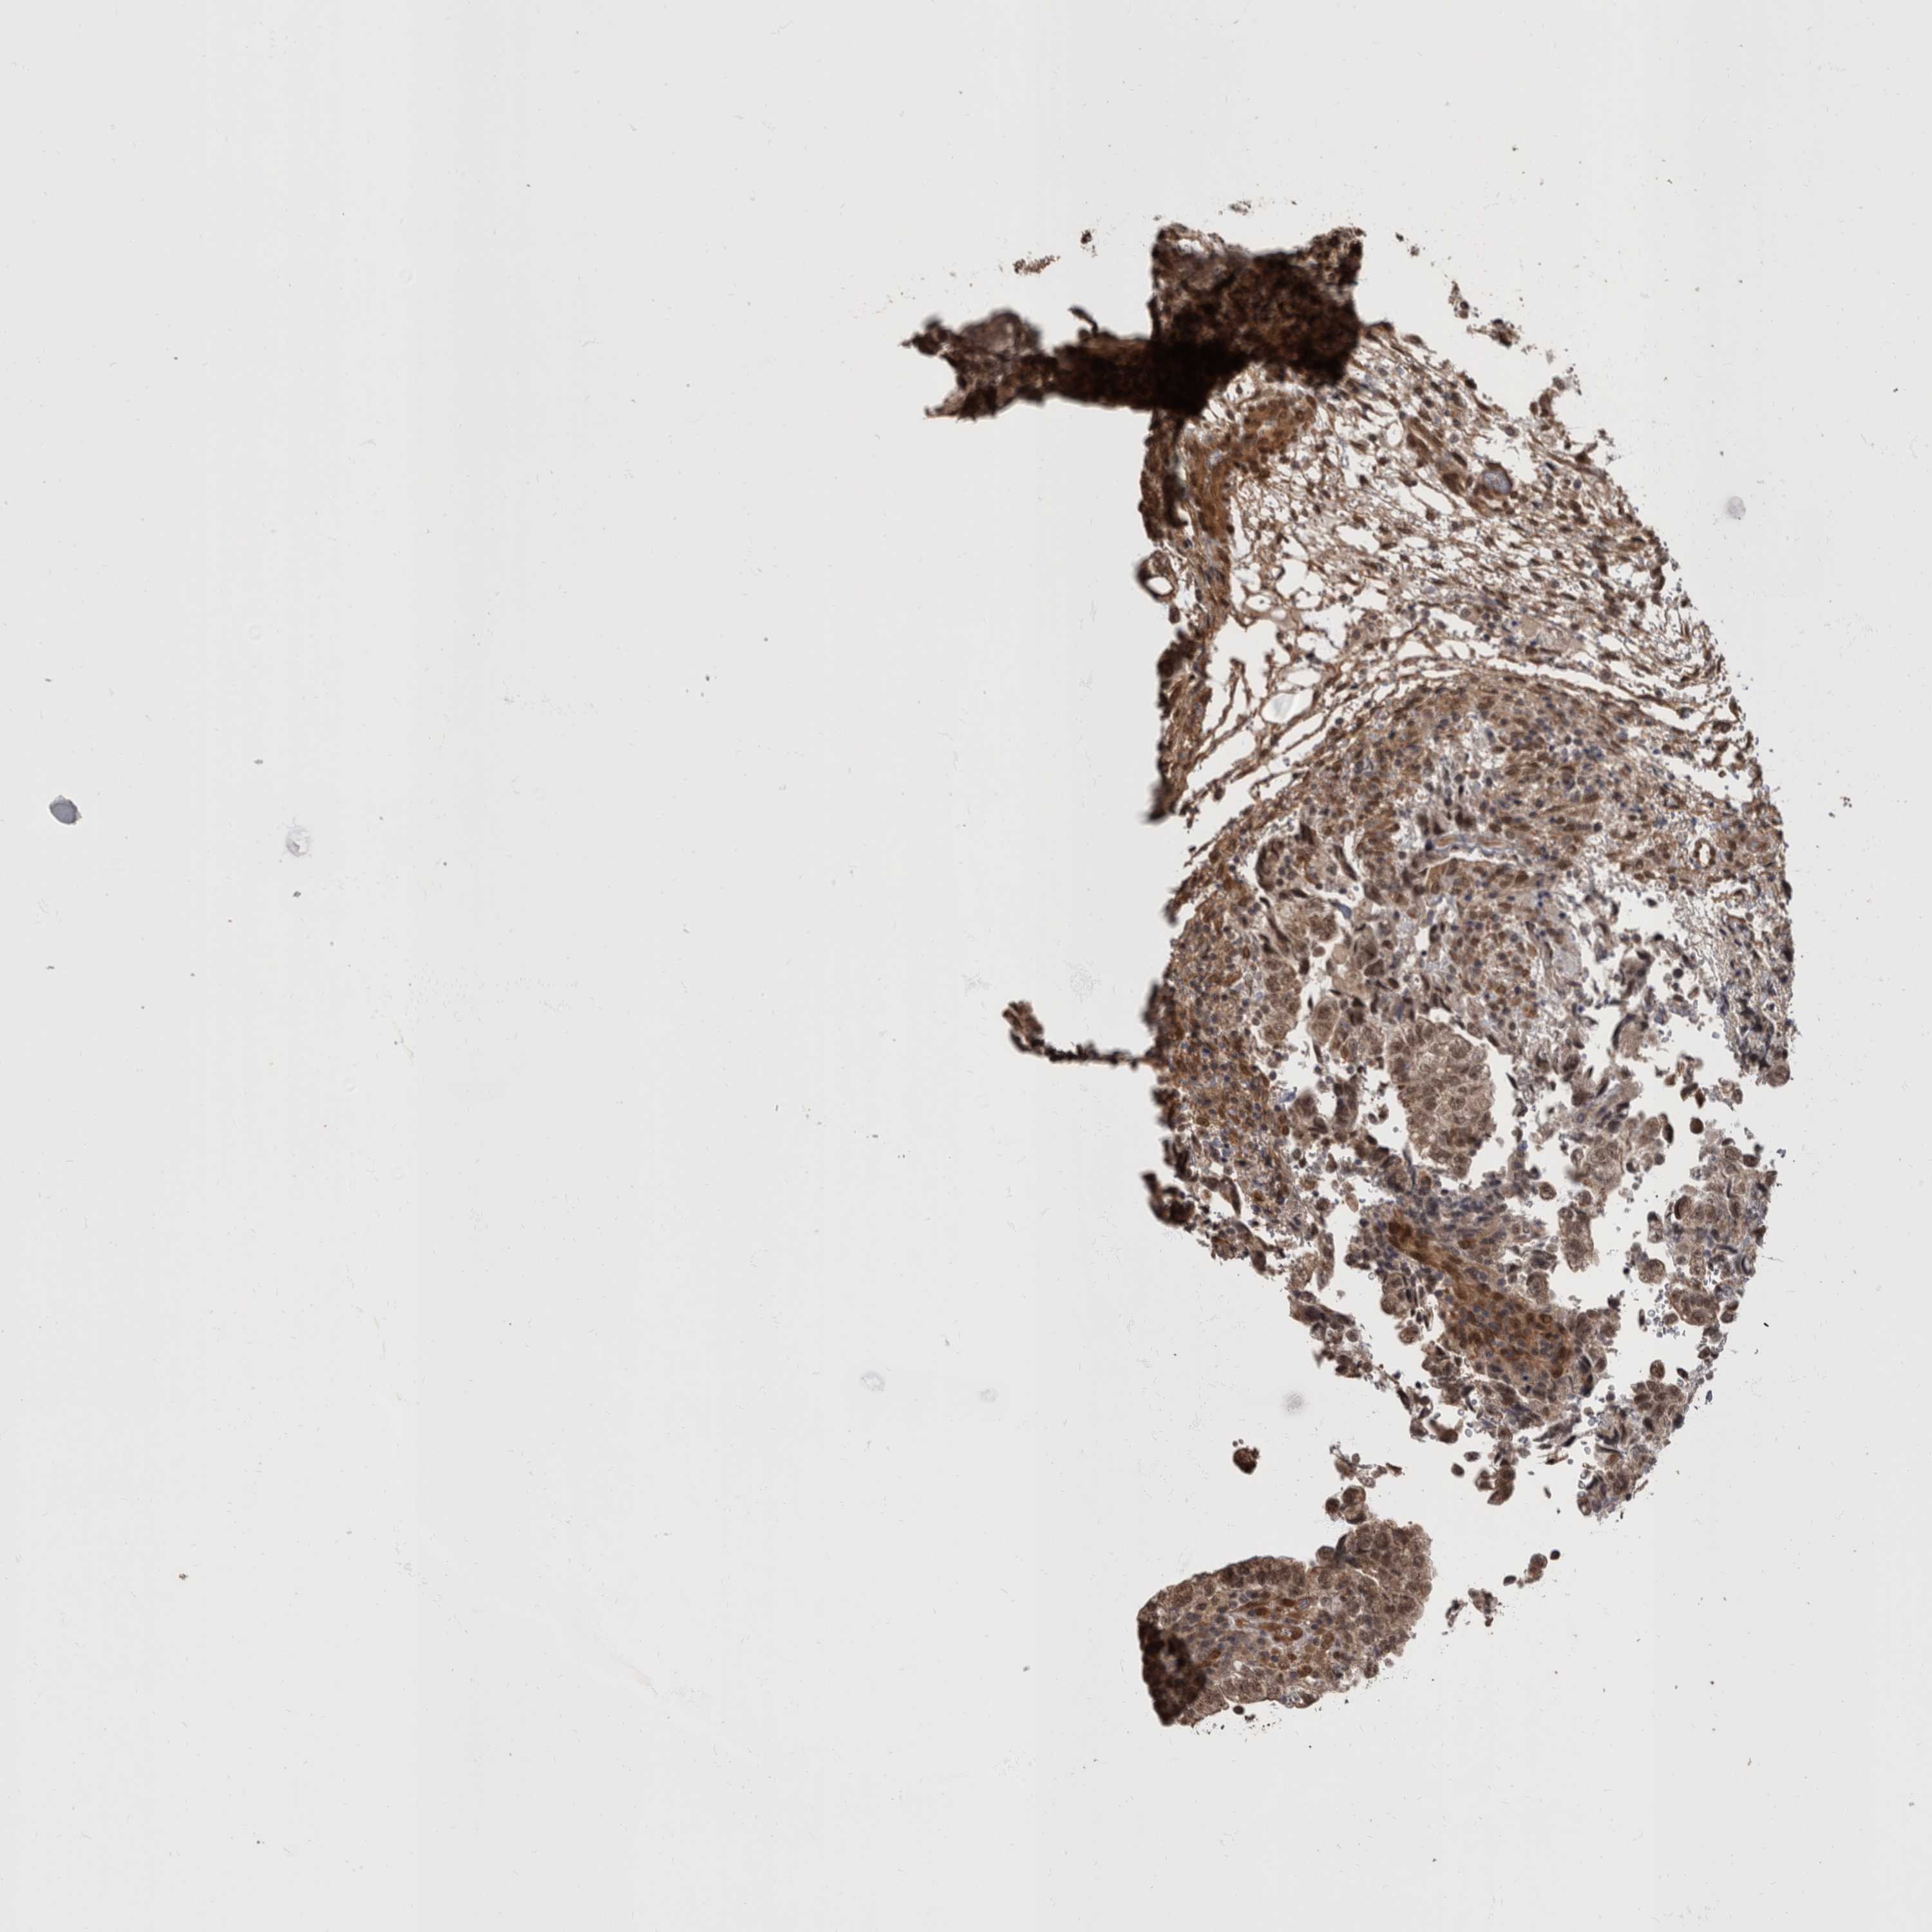

TESTIS CANCER - Protein expressioni

A mouse-over function shows sample information and annotation data. Click on an image to view it in a full screen mode. Samples can be filtered based on level of antibody staining by selecting one or several of the following categories: high, medium, low and not detected. The assay and annotation is described here.

Note that samples used for immunohistochemistry by the Human Protein Atlas do not correspond to samples in the TCGA dataset.

Antibody stainingi

Antibody staining in the annotated cell types in the current human tissue is reported as not detected, low, medium, or high, based on conventional immunohistochemistry profiling in selected tissues. This score is based on the combination of the staining intensity and fraction of stained cells.

Each image is clickable and will lead to virtual microscopy that enables deeper exploration of all samples and also displays staining intensity scores, fraction scores and subcellular localization as well as patient and tissue information for each sample.

Antibody HPA026441

Antibody CAB013090

Staining

High

Medium

Low

Not detected

Intensity

Strong

Moderate

Weak

Negative

Quantity

>75%

75%-25%

<25%

None

Location

Nuclear

Cytoplasmic/membranous

Cytoplasmic/membranous,nuclear

Carcinoma, Embryonal, NOS

Seminoma, NOS